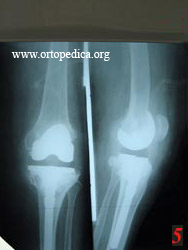

5. Тот же сустав после ревизионного эндопротезирования